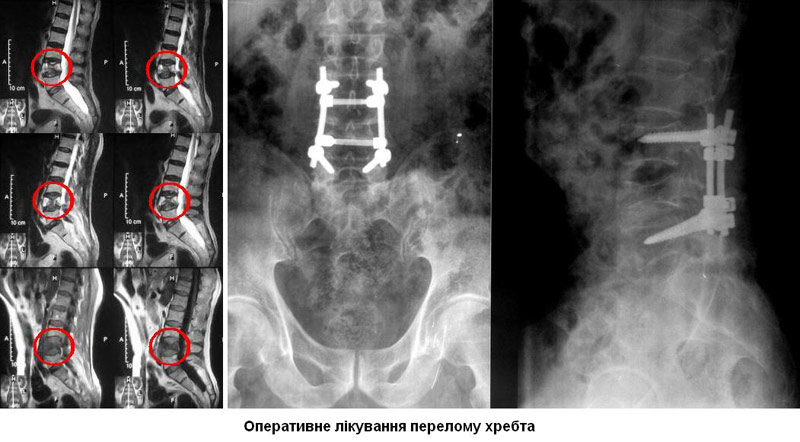

- Операція. Часто необхідно проведення термінової операції, щоб видалити фрагменти кісток, сторонні тіла, грижу міжхребцевого диска або зламані фрагменти хребця, що здавлюють вміст хребетного каналу. Операція також може знадобитися для стабілізації хребта, щоб запобігти появі болю або деформації. Існують деякі протиріччя щодо кращого часу проведення операції. Деякі хірурги вважають, що її необхідно виконувати раніше, інші вважають, що безпечніше почекати кілька днів до проведення будь-якої операції. Науково обгрунтованих доказів переваг ранніх (ургентних) операцій не отримано.

Мета операції - стабілізація хребта металевими конструкціями (імплантантами). Наша клініка була першою в СНД, яка застосувала сучасні конструкції при переломах хребта. Нині ми використовуємо імпортні конструкції типу CD Horison Legacy (США), Atlantis (США), Sextant (США), Socore (Франція). Операції вимагають складної рентгенівської техніки та спеціального інструментарію. При неускладнених переломах хребта хворі можуть ходити після таких операцій уже на другий - третій день. Також в Міжнародному центрі нейрохіургіі вперше в Україні впроваджено метод мініінвазивних операцій при переломах хребта.